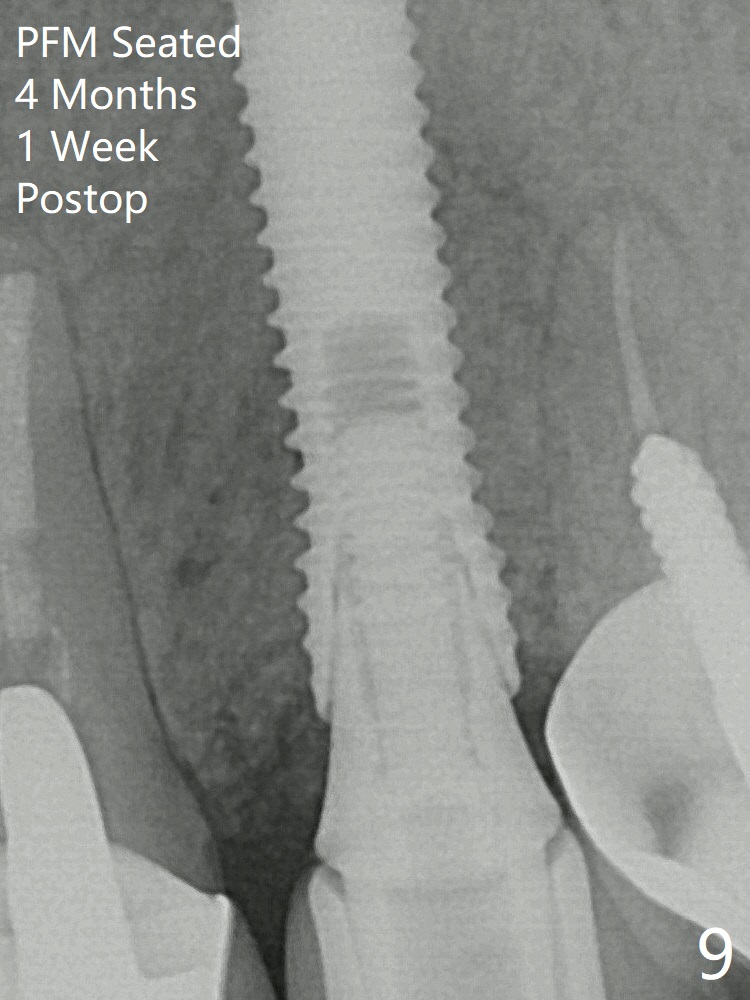

In spite of severe apical infection (Fig1,2 *), a thin narrow strip of the buccal plate (arrowheads, corresponding to the keratinized gingiva) is present when the tooth #11 is extracted. The thin bone keeps the bulging alveolus, i.e., reservoir for bone graft (Vanilla/Osteogen Fig.4 *) after placement of a 3.8x16 mm implant (Fig.3,4). A 4.5x1 mm temporary abutment, placed and trimmed for an immediate provisional, seems to be short in cuff. When an implant is placed deep to prevent periimplantitis, the cuff should be longer, i.e., 3 mm. X-ray should be taken for the depth confirmation after temporary abutment placement. Fig.3: a 2 mm drill in place, 18 mm in bone vs. 16 mm of implant placed ~ 2 mm subcrestal (Fig.4). A narrow implant (3.8 mm) is chosen over 4.5 mm because of the extensive buccal plate defect. While the hard tissue around the implant seems to be healthy 5 months postop (Fig.7), the soft tissue is not (Fig.8). Indeed PFM helps shade match in this case as well (Fig.9,10). Switching abutments (from temporary to cemented) makes it difficult to seat the crown. Post cementation X-ray leaves record for future contact loosening.